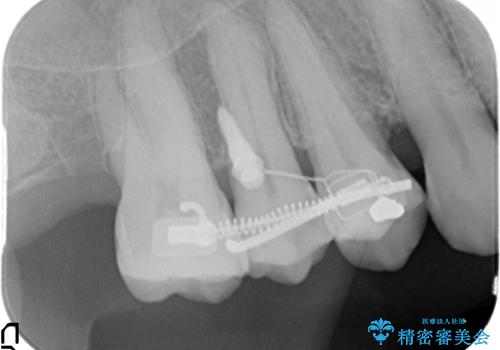

部分矯正を含む 歯周病治療 (再生治療・歯周ポケット除去・MTM・連結補綴)

検査の結果、強い歯ぎしりによる歯の周囲の骨の吸収が認められたため歯槽骨の再生・歯周ポケットの除去・力に対抗する連結補綴・補綴前処置としての小矯正を計画します。

今回連結補綴を行うにあたり、歯周病の問題を解決するために再生療法・歯周ポケット除去手術を、またより歯の神経を保存し力に対抗できる環境を整えるために小矯正を行い精度の高いメタルボンドクラウンを製作することができました。